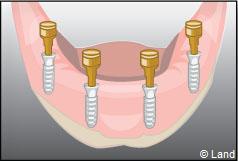

Les implants peuvent aussi servir à stabiliser un appareil amovible au maxillaire supérieur comme au maxillaire inférieur. Dans ce cas, les implants retiennent la prothèse amovible par des systèmes d’attachement.

Deux techniques sont possibles. Elles font appel à la barre de rétention ou aux boutons-pressions.